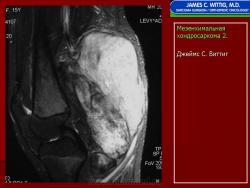

Рентгенологическое изображение при мезенхимальной хондросаркоме не обладает специфичностью и во многом сходно с обычной классической хондросаркомой, представлено литическим очагом без четких границ.

Рентгенологическая картина довольно разнообразная: это литические очаги деструкции, вздувающие кость, иногда с ячеистым или остатками ячеистого строения, наличием остатков от неполностью разрушенных костных структур, иногда с участками обызвествления и окостенения. При околокостном расположении опухоли бывает виден различной интенсивности очаг в мягких тканях с более равномерным или очаговыми формами обызвествления и окостенения с нечеткими контурами, прилежащий кости или охватывающий ее.